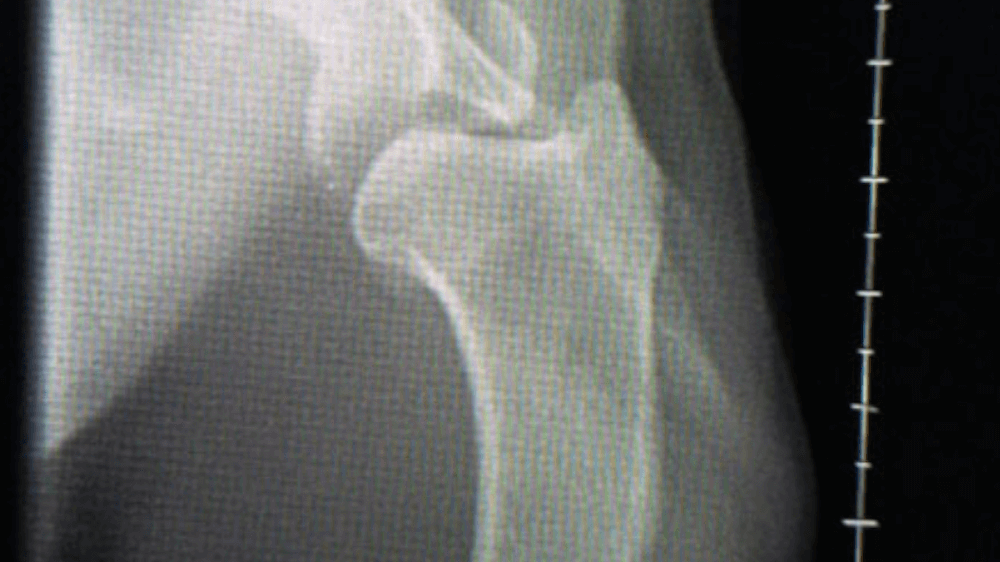

Y Fracture Repair

In a Springer Spaniel.